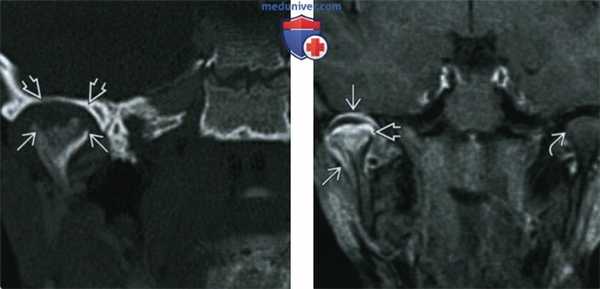

(Слева) При корональной КТ в костном окне у четырехлетней девочки, страдающей ювенильным идиопатическим артритом (ЮИА), визуализируются эрозии мыщелка нижней челюсти справа (эрозии существуют длительное время, края мыщелка неровные). Отмечается также расширение и уплощение суставной ямки.

(Справа) При МРТ Т1ВИ FS с КУ b корональной проекции у этой же девочки с ЮИА определяется выраженное контрастное усиление пораженного сустава, а также костного мозга правого мыщелка нижней челюсти, обусловленное его воспалением. Со стороны левого ВНЧС не определяется воспалительных изменений, мыщелок и суставная ямка не выглядят патологически измененными. (Слева) При МРТ Т1ВИ FS с КУ в кососагиттальной проекции у пациентки 21 года с ювенильным идиопатическим артритом определяется уменьшенный мыщелок нижней челюсти с деформированными склерозированными краями с низкой интенсивноаью сигнала. Суставная ямка плоская и расширенная. Контрааное усиление, обусловленное воспалением, отсутствует. Отмечается небольшой остеофит в передних отделах (признак вторичного остеоартроза).

(Справа) При МРТ Т1ВИ FS с КУ b корональной проекции у этой же девочки с ЮИА определяется выраженное контрастное усиление пораженного сустава, а также костного мозга правого мыщелка нижней челюсти, обусловленное его воспалением. Со стороны левого ВНЧС не определяется воспалительных изменений, мыщелок и суставная ямка не выглядят патологически измененными.